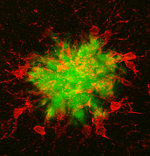

Eine Aktivierung des Immunsystems des Gehirns ist Teil fast aller neurologischer Erkrankungen und das Auftreten der Alzheimer-Demenz (AD) wurde kürzlich mit genetischen und epigenetischen Veränderungen von immun-relevanten Genen in Verbindung gebracht. Dies deutet auf eine signifikante Beteiligung des Immunsystems an der Alzheimer-Demenz hin. Die Immunantwort, die als Teil der Alzheimer-Erkrankung auftritt, wird hauptsächlich durch die Hirn-ansässigen Makrophagen, sogenannten Mikroglia, vermittelt, und diese Zellen sammeln sich besonders um die unlöslichen Ablagerungen an, die als Teil der Erkrankung im Gehirn auftreten. Jedoch sind verschiedene Aspekte der Rolle von Mikroglia in der Alzheimer-Pathogenese weiterhin ungeklärt. Weiterhin ist unklar, wie Entzündungsprozesse außerhalb des zentralen Nervensystems die Immunantwort des Gehirns beeinflussen können.

Zu diesem Zweck verwenden wir verschiedene Modelle der peripheren Entzündung und profilieren die Immunantwort der Mikroglia auf sekundäre Reize, einschließlich pathologischer Veränderungen in neurodegenerativen Krankheitsmodellen. Wir isolieren Mikroglia aus dem adulten und gealterten Gehirn und untersuchen deren molekulare Profile (transkriptional, epigenetisch) und Funktionen (phagozytisches Verhalten und Freisetzung entzündlicher Mediatoren). Zusammen mit der Unit Molekulare Bildgebung verwenden wir Multiphotonen-Mikroskopie, um mikrogliales Verhalten im lebenden Gehirn unter entzündlichen Bedingungen zu untersuchen.